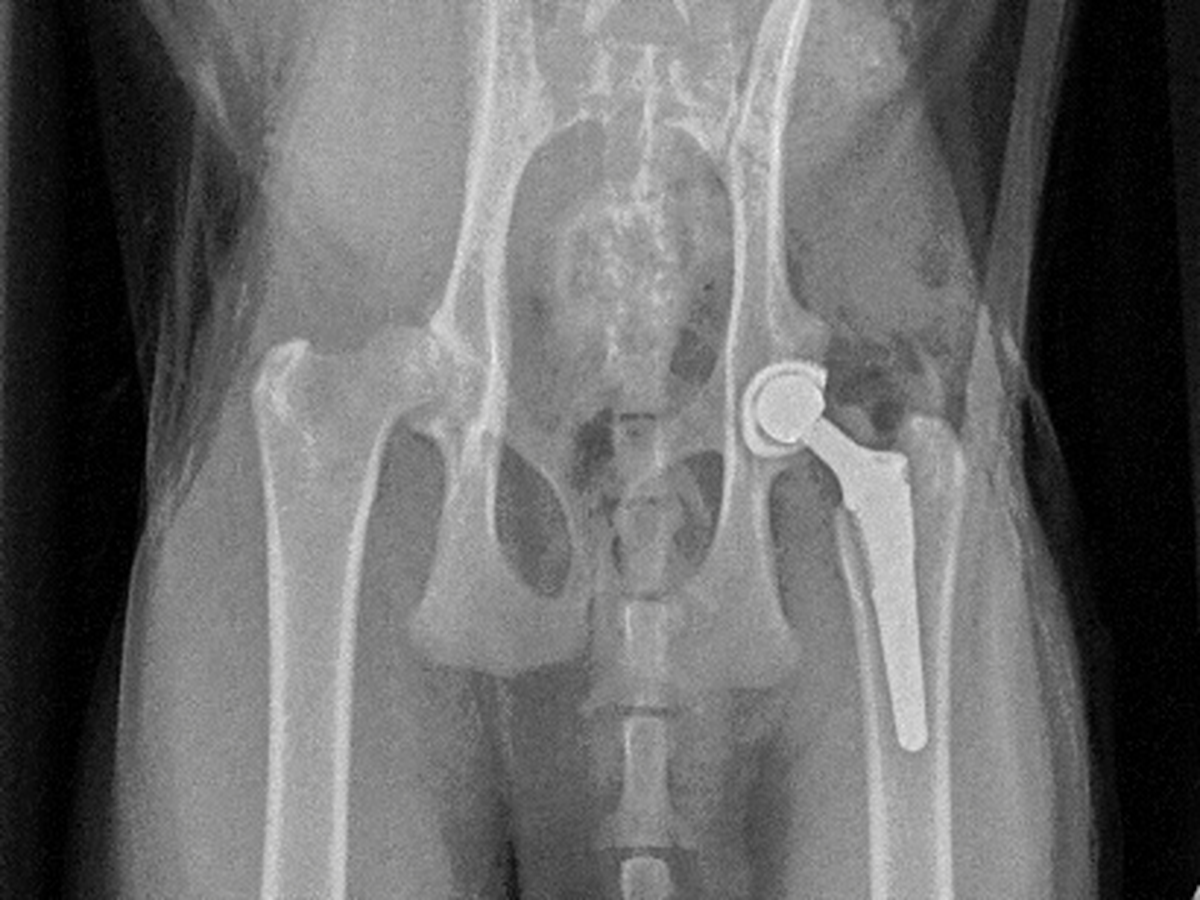

Frank, our sweet and energetic cat, recently underwent a total hip replacement, a rare and complex surgery for cats. Unfortunately, despite the procedure being a success, he experienced one of the riskiest complications—a femur fracture caused by the implant, a 5% chance that became our reality.

We did everything we could to keep him stable, but his repair (a plate and wire) started failing the first night. Now, Frank is undergoing his third emergency surgery to repair the fracture again and ensure his leg heals properly.